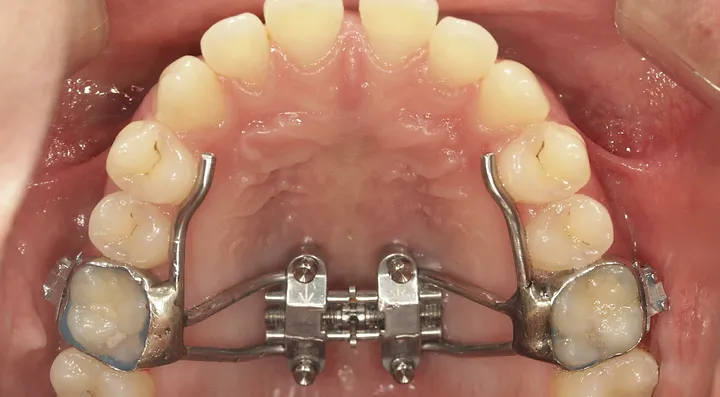

if you have bad transverse maxillary deficiency then definitely look into it. i want to try and get this however i dont know if i'll be eligible seeing as how my lower arch is like 10mm smaller than my maxillary arch.

look how the maxilla was ripped apart on this one holy chit